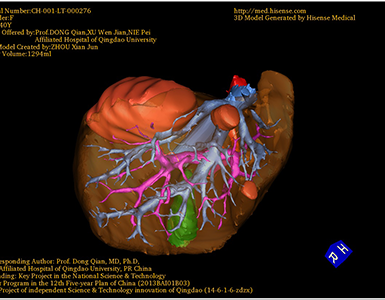

术前三维重建:重建图片

通过调节窗宽窗位调整CT序号,对肿瘤,肝实质,胆囊,下腔静脉,肿瘤,肝动脉、门静脉及肝静脉等进行三维重建;系统自动计算肿瘤体积和肝脏体积。

模拟手术操作,自动计算切除肿瘤体积。肝脏体积为1294ml,肿瘤体积为158.5ml,肿瘤体积为肝脏体积的12.2%,通过比对40-50岁正常肝脏体积为1368.38±279.24 ml,通过术前模拟手术,精准判断切除后剩余肝脏体积能耐受,避免肝衰竭发生。